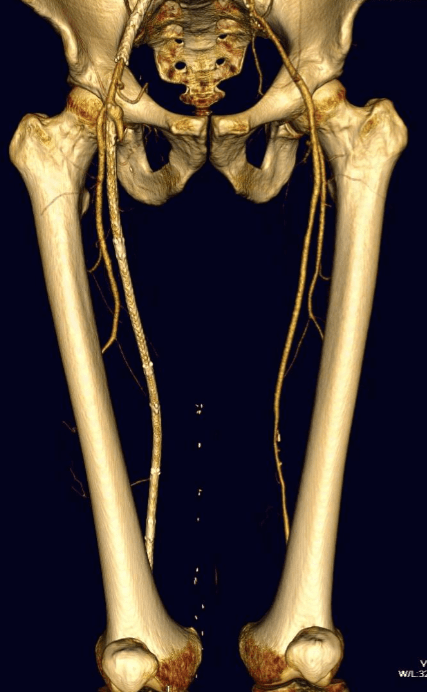

The patient is 70 year old woman with prior history of smoking who developed severe claudication and near rest pain. She was unable to walk more than 50 feet before having to stop due to severe leg pain. On exam, neither femoral artery pulses were palpable. PVR’s (pulse volume recordings) and ABI’s (ankle brachial index) are shown below.

PVR’s demonstrate the presence of severe inflow (aortoiliac occlusive disease or AIOD). CTA was acquired and the findings were consistent with the PVR’s.

There was diffuse bilateral iliac atherosclerotic plaque with occlusion of the right common femoral artery and left common and external iliac artery. The 3DVR (three dimensional virtual reality) reconstruction image below shows this as well as the abdominal and pelvic wall collaterals feeding the legs around the occluded iliofemoral system.

Plans were made to perform a hybrid common femoral and profunda femoral endarterectomy, remote external iliac artery endarterectomy (EndoRE), and common iliac artery stenting. The specific challenges to this case was getting into and staying in the true lumen. Typically, this is easiest to achieve from a left arm access with wires being pushed antegrade, but in a smaller person, particularly woman, this increases the chances for access site complications. My plan was to expose both common femoral arteries and get control of the external iliac arteries at the inguinal ligament and the profunda femoral arteries at the point the proximal plaque dissipated -typically at the second branch point, and then get micropuncture access of the right iliac system by accessing from the common femoral plaque. This would give me true lumen access, and with a sheath and curved catheter (VCF in this case, but a similarly shaped OMNI Flush catheter would do as well), wire access up and across the occluded left iliac system could be achieved and the wire retrieved from the left common femoral artery. This up and over access with the wire allows for control of the aortic bifurcation and both iliac systems.

The 3DVR reconstruction images are shown below, with the comparison to preop shown in the first image of this blog entry: